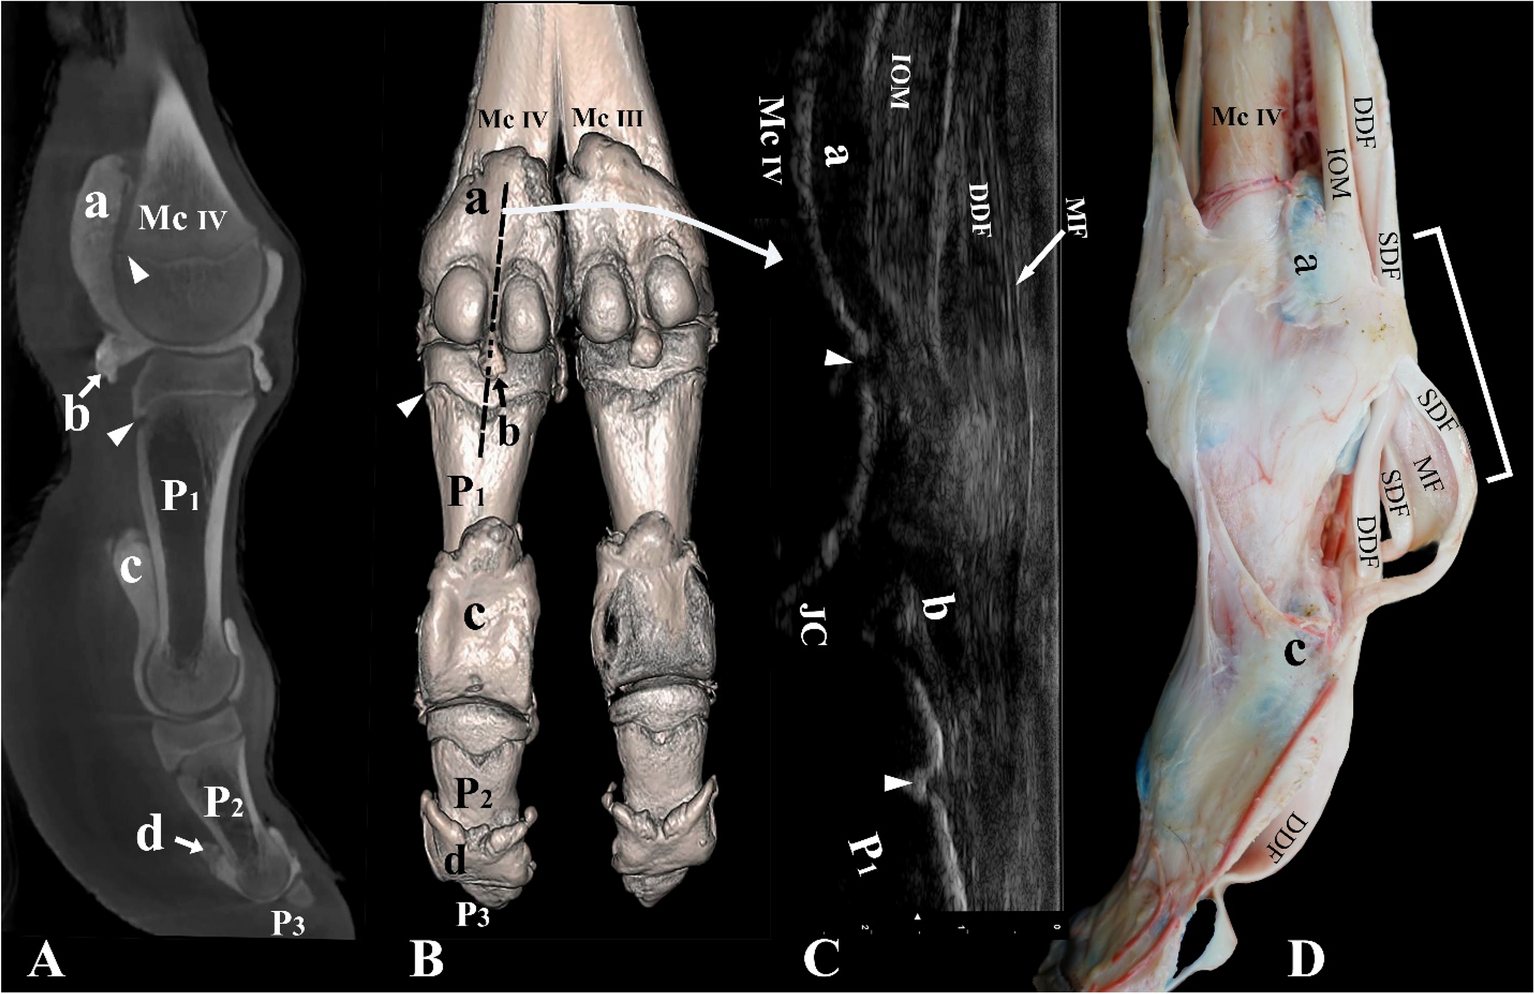

Figure 3

From: Arthrocentesis approaches to the phalangeal joints of the one humped camel (Camelus dromedarius)

Palmar and lateral view of the left distal forelimb and digit IV. (A) Sagittal plane CT image, (B) three-dimensional reconstruction (the black dotted line indicates the placement of the ultrasound probe between the two proximal sesamoid bones), (C) longitudinal palmar ultrasound image of the metacarpophalangeal joint, and (D) dissection. Mc III distal end of metacarpal bone III, Mc IV distal end of metacarpal bone IV, P1 proximal phalanx, P2 middle phalanx, P3 distal phalanx, a proximal palmar pouch of the metacarpophalangeal joint, b distal palmar pouch of the metacarpophalangeal joint, c proximal palmar pouch of the proximal interphalangeal joint, d proximal palmar pouch of the distal interphalangeal joint, IOM interosseous medius muscle, SDF superficial digital flexor tendon, DDF deep digital flexor tendon, MF manica flexoria, JC joint cavity. The white arrowheads indicate the epiphyseal lines, and the white square bracket indicates the ultrasound area on image (D).